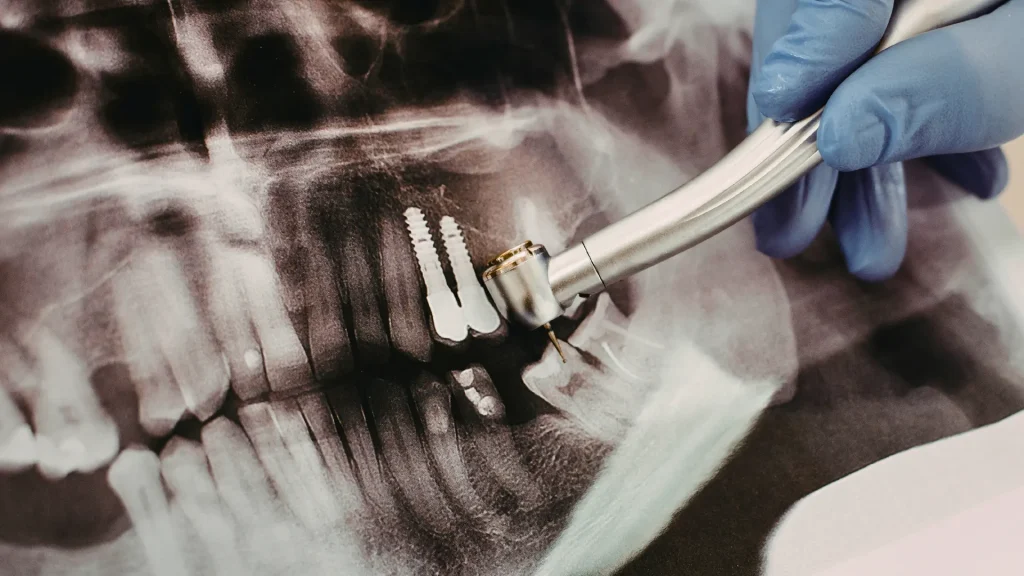

Bir implant, titanyum bir vidanın çene kemiğine yerleştirilmesiyle başlar. Vidanın sağlam kalması için kemiğin bu yabancı cismi zamanla benimsemesi, yani osseointegrasyon (implantın kemikle kaynaşması) sürecinin eksiksiz tamamlanması gerekir. Bu sürecin başarısı; çene kemiğinin yoğunluğuna, ağız dokusunun sağlığına ve hastanın genel iyileşme kapasitesine doğrudan bağlıdır.

- 3D dental tomografi (CBCT): Çene kemiğinin yüksekliği, genişliği, yoğunluğu ve sinir-sinüs gibi anatomik yapılarla ilişkisi milimetrik hassasiyette analiz edilir.